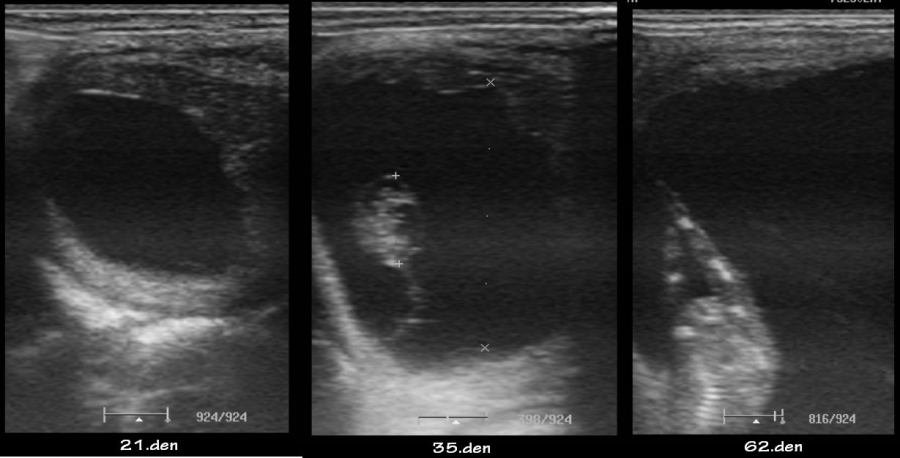

embryo kolem 21.dne

Embryo 31. den